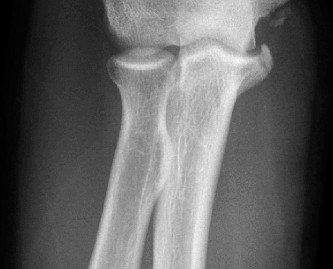

Treat a patient with infected total shoulder arthroplasty? CASE 21 A 70-year-old, right-hand-dominant female presents to clinic complaining of 4 years of gradually worsening chronic right shoulder pain and stiffness. She says the pain is worse at night and with any range of motion, denies a history of trauma, pain in other extremities, or numbness or tingling of the right upper extremity. She notes that her mother suffered from rheumatoid arthritis that affected her shoulder. Physical examination reveals decreased muscle bulk over the right supra- and infraspinatus fossae compared to the contralateral side, limited active and passive ROM, marked weakness with external rotation, and 4+/5 strength with shoulder abduction. X-rays of the right shoulder are shown in Figures 2–58 and 2–59.

The correct answer is (C). Rotator cuff tear arthropathy consists of a combination of rotator cuff insufficiency, glenohumeral joint degenerative changes, and superior humeral head migration. It is more common in women and also more often found on the dominant side. The patient’s clinical examination with weakened external

rotation and muscle atrophy signaling incompetent supra- and infraspinatus muscles point to rotator cuff insufficiency, and her plain films reveal narrowed glenohumeral joint space as well as superior migration of the humeral head. Choice D is incorrect because, while radiographs would show narrowing of the glenohumeral joint space, they would also likely show numerous osteophytes and posterior wear of the glenoid. Choice B is incorrect because, while adhesive capsulitis does present as decreased active and passive range of motion, the patient’s constellation of symptoms pointing towards rotator cuff insufficiency along with the radiographs make cuff tear arthropathy the more likely choice. Finally, Choice A is incorrect because even though she has a positive family history of rheumatoid arthritis, it is less likely to present only in a single joint. Also, rheumatoid arthritis on radiography appears more as an erosive process without the characteristic superior migration of the humeral head.

The correct answer is (A). Superior migration of the humeral head would be most indicative of chronic rotator cuff insufficiency associated with cuff tear arthropathy, as it is a direct result of the inability of the rotator cuff tendons to help maintain the humerus in its normal position. Acetabularization of the undersurface of the acromion is commonly associated with superior migration of the humeral head found in rotator cuff tear arthropathy, and can be assessed using the Hamada classification, which is based on measurements of the acromiohumeral interval on radiography (Table 2–8). Choices B and C are incorrect because, while narrowed glenohumeral joint space and subchondral sclerosis are associated with rotator cuff arthropathy on radiographs, they indicate degenerative joint changes rather than chronic rotator cuff insufficiency. Choice D is incorrect because it is not a specific sign of rotator cuff arthropathy.